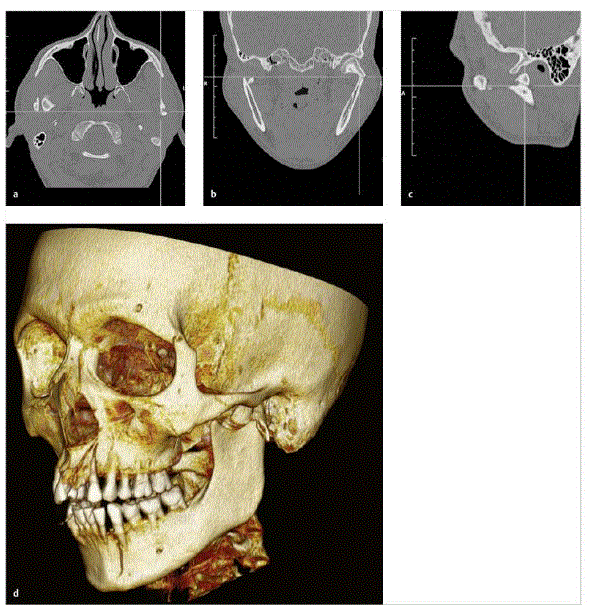

Welche Aufnahme ist es ?

Welche Ebene ?

Diagnose ?